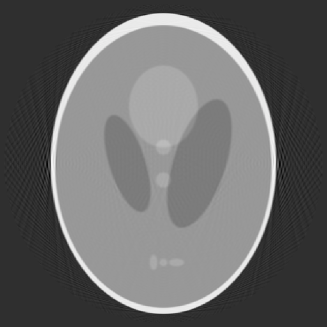

For our first numerical example, we use the classical head phantom of Shepp-Logan [17]. This phantom is shown in Figure 2.

The left figure is the original phantom. The right figure is the reconstruction by OPED based on the full data with , which means 251 views with angles equally distributed over and 251 rays per view, and the size of the reconstruction is pixels. Reconstruction based on the full data has been discussed in [4, 20, 21], we will not give further details here as our purpose is to demonstrate the feasibility of our method on the limited angle problem.